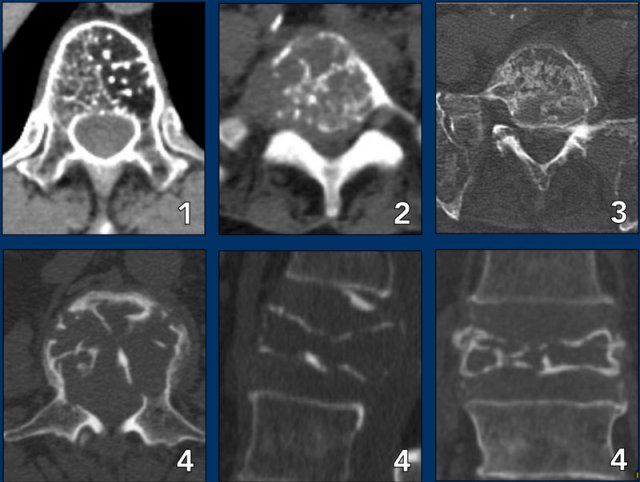

Spine lesions

Here some typical examples of bone tumors in the spine.

1. Hemangioma.

2. Metastasis.

3. Multiple myeloma.

4. Plasmocytoma: vertebra plana.

This 'Mini Brain' appearance of plasmacytoma in the spine is sufficiently pathognomonic to obviate biopsy (9).

More examples

1. ABC

2. Chondrosarcoma

3. Metastasis of breast cancer

4. Osteoblastoma